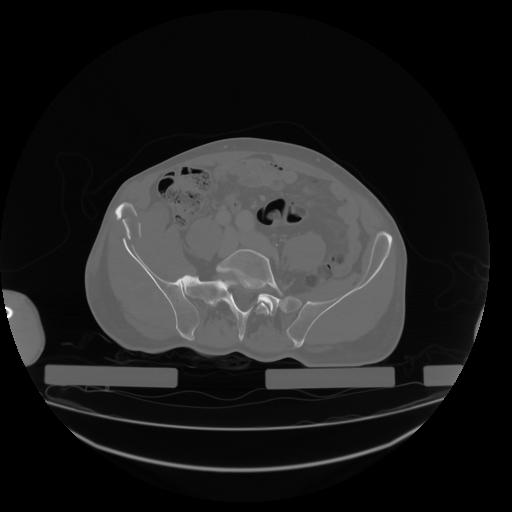

27 CUERPO,CE,Axial,3.0,CUERPO,,